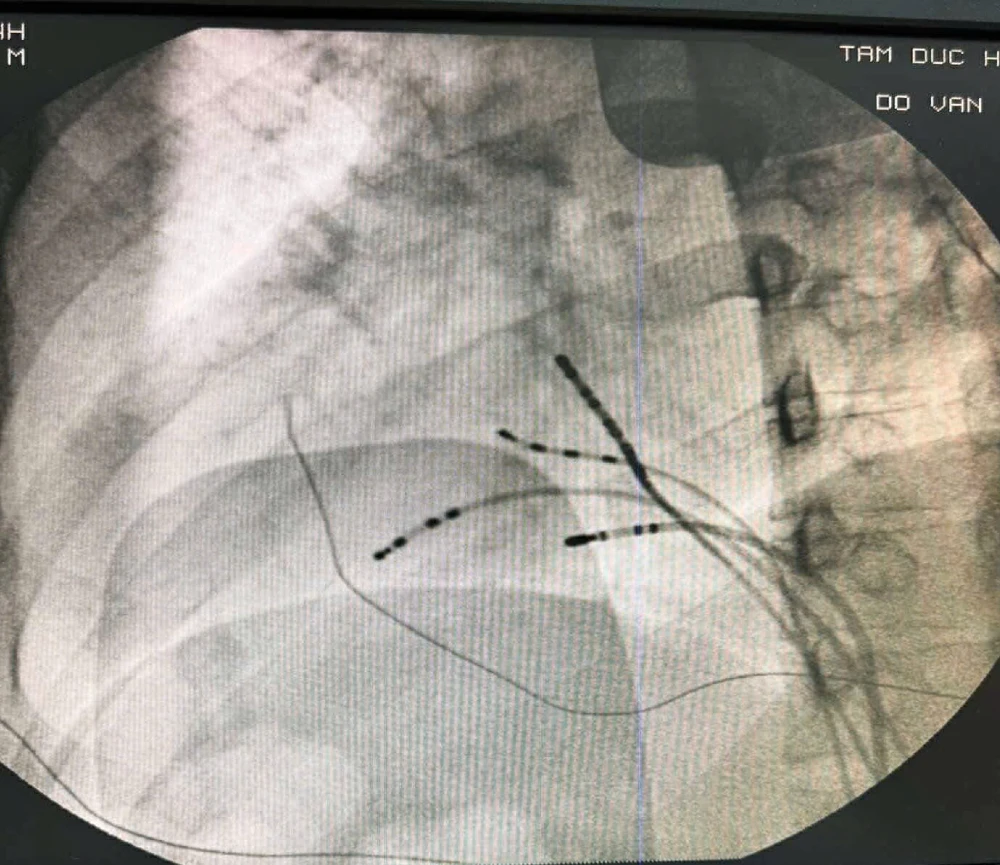

Sau khi đánh giá cẩn thận cấu trúc tim và xác định chỉ định cắt đốt đường dẫn truyền phụ là cần thiết, đội ngũ bác sĩ tại Bệnh viện Tim Tâm Đức đã quyết định thực hiện thủ thuật thăm dò tiên tiến 3D bằng hệ thống dựng hình 3 chiều carto.

Các catheter xoang vành và các buồng tim được dựng hình lại như hình vẽ, và tiến hành tìm đường dẫn truyền phụ bằng kinh nghiệm suy luận giải phẫu tim và không gian 3D.

Tại vị trí thành sau của vòng van 3 lá chúng tôi ghi nhận điện thế bất thường của đường dẫn truyền phụ. Tiến hành cắt đốt vị trí này chấm dứt hoàn toàn đường dẫn truyền phụ và bệnh nhân không còn những cơn nhịp nhanh bất thường nguy hiểm.

Ca phẫu thuật không chỉ thành công mà còn thể hiện sự kết hợp hoàn hảo giữa kiến thức chuyên sâu, kinh nghiệm lâm sàng và công nghệ hiện đại.

Ngoài ra, nhờ hệ thống 3D giúp thủ thuật phức tạp được thực hiện an toàn, nhanh và ít dùng đến tia X. Điều này rất có lợi cho người bệnh.